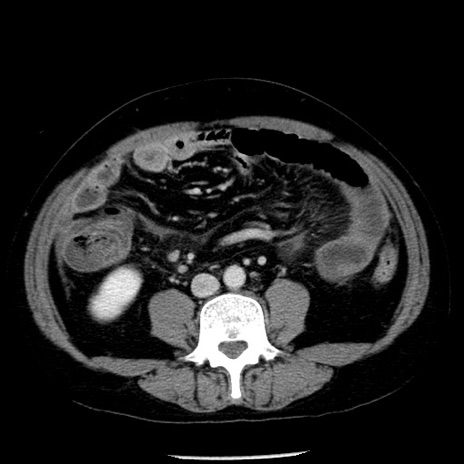

症例29(横断像)

【症例】40歳代男性

【現病歴】2日前から胃痛あり。徐々に周期的な激痛に変化した。本日になっても激痛があるため受診。

【身体所見】意識清明、BT 38-39℃台あり、腹部:膨満、やや硬、右下腹部に圧痛あり。

【データ】WBC 8500、CRP 23.26